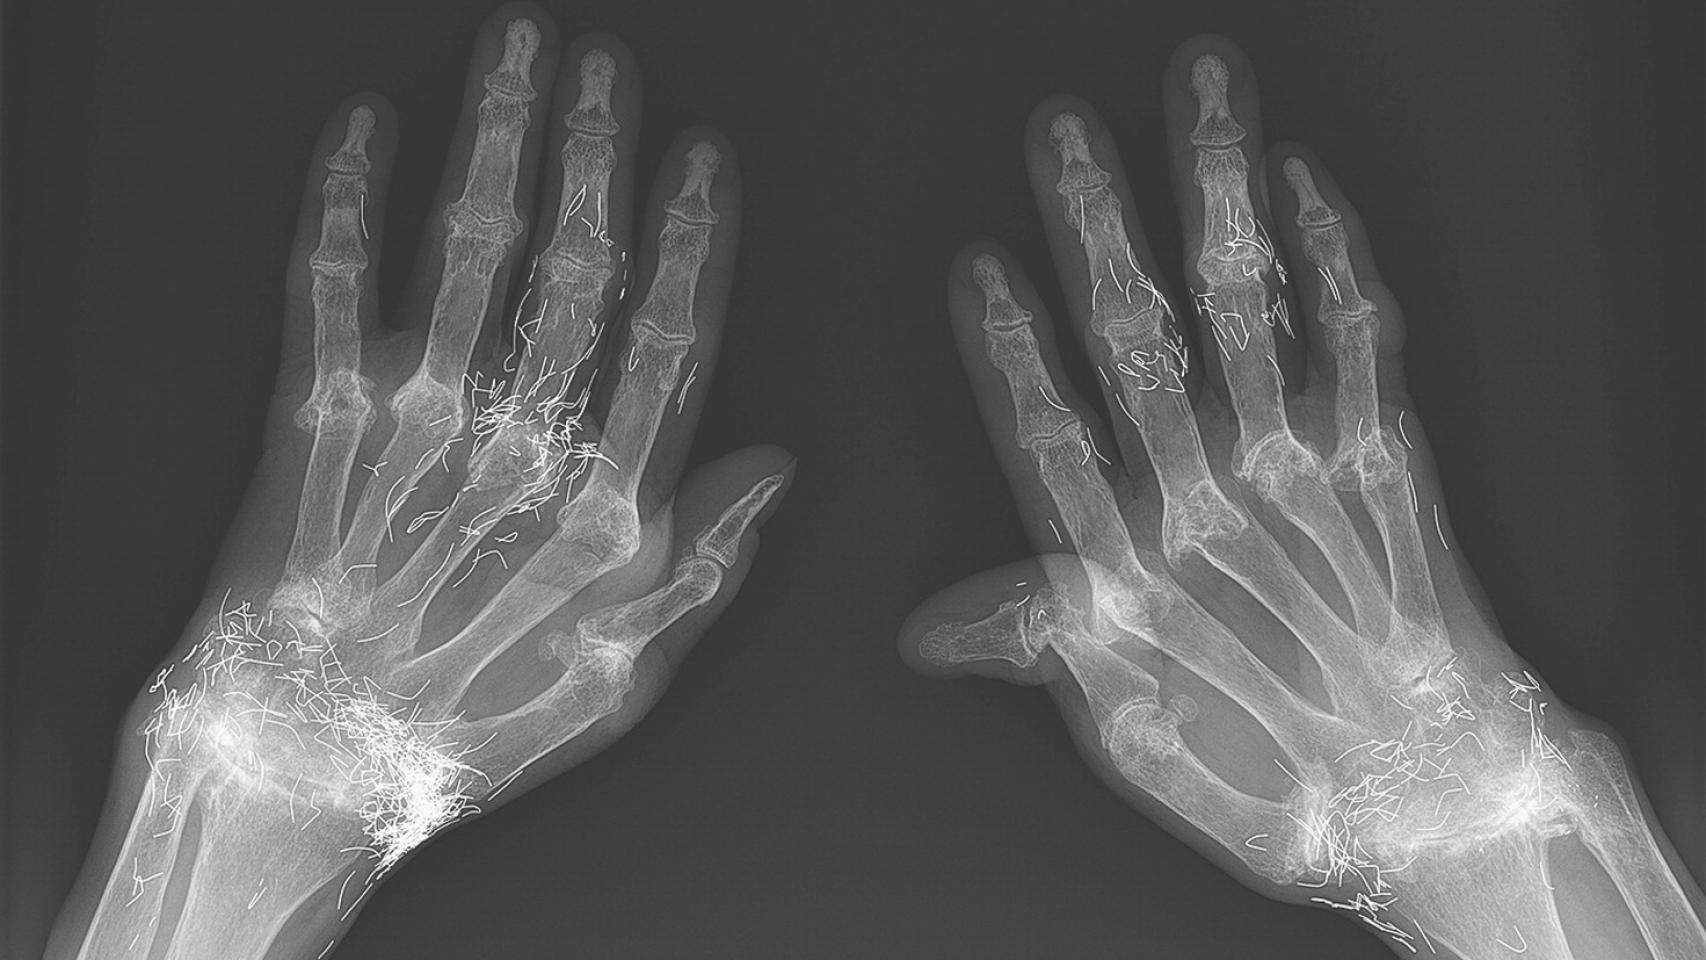

Como parte del estudio de su dolor, se le realizaron una serie de radiografías. Y es ahí dónde se manifestó el extraño hallazgo: filamentos de oro brillando en el interior de las muñecas y los dedos de la paciente. Y es que la mujer había recurrido a los remedios tradicionales antes de acudir a los médicos, con deplorables consecuencias.

Cuando empezaron los dolores, la paciente intentó paliarlos mediante la toma de antiinflamatorios, como el ibuprofeno. También recurrió a la medicina alternativa, intentando aliviar su dolor mediante acupuntura con hilos de oro. Dicha práctica tiene ciertas similitudes con la acupuntura tradicional, en la cual se insertan agujas muy finas por todo el cuerpo. En esta variante, sin embargo, los pequeños filamentos se cortan y se insertan en la piel mediante agujas de acupuntura, y quedan dentro del cuerpo.

Según refiere el informe de este caso, esta práctica usa mucho en la zona del este de Asia y en todo el mundo como forma de tratar el dolor articular. Sin embargo, el caso de esta mujer era llamativo por dos razones: la gravedad de su artritis reumatoide, la cual le causó deformidades a nivel de manos y pies; y el hecho de que los hilos de oro se insertaron en casi todas las articulaciones que tenía de formadas en sus manos.

A pesar de todo, la inserción de estos finos hilos de oro no parece haber ocasionado un empeoramiento de la enfermedad, según el reporte del caso. Aún así, los autores destacan el hecho de que no existan demasiados informes sobre los posibles efectos adversos de esta práctica alternativa.